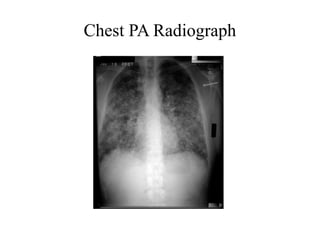

Chest PA Radiograph